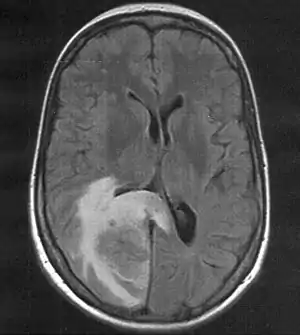

![]() | |

| Skull MRI (T2 flair) of a brain metastasis with accompanying edema | |